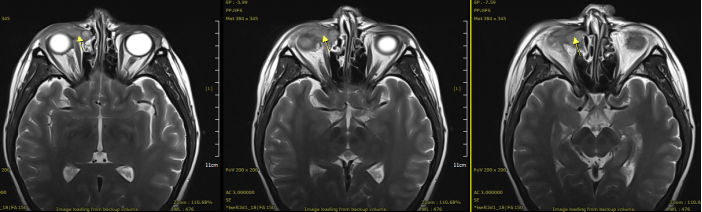

General Information: A 44-year-old female patient presented with a round mass about the size of a mung bean at the root of the right nostril, accompanied by tearing. There was no redness, swelling, pain, significant secretion, visual impairment, headache, nausea, vomiting, orbital pain, diplopia, or visual distortion. The diagnosis was confirmed by orbital MRI, endoscopic biopsy of the right lacrimal sac tumor, and PET-CT.

Figure 1: Pre-treatment (16mm × 22mm × 28mm)